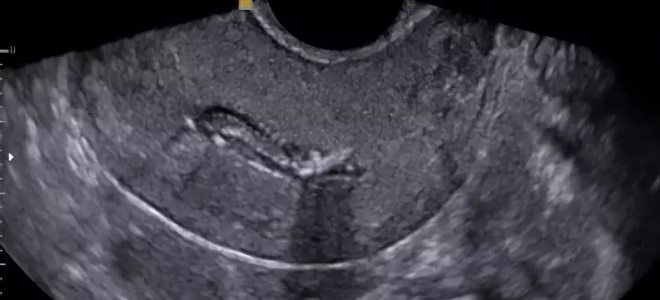

УЗИ матки после родов

Если врач подозревает, что в матке после родов остались кровяные сгустки, он назначает женщине ультразвуковое исследование. Во время этой процедуры специалисты тщательно исследуют полость матки, а также оценивают её размеры, что позволяет определить степень сокращения органа. Обычно для обследования используется трансабдоминальный метод, при котором датчик располагается на передней стенке живота.

Особое внимание уделяется состоянию полости матки. В норме на 2-3 сутки она должна иметь щелевидную форму или быть слегка расширенной из-за небольшого количества крови, скопившейся в её верхней части. На 5-7 сутки сгустки крови перемещаются в нижние отделы.

К числу возможных отклонений от нормы, свидетельствующих о наличии сгустков в матке после родов, относятся:

- значительное расширение полости;

- остатки плацентарной ткани;

- обильное скопление крови.